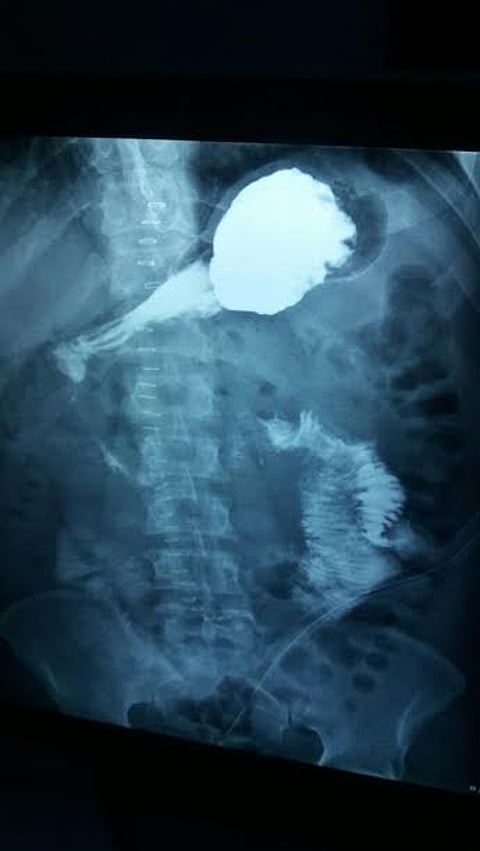

وجرى استدعاء الفريق الجراحي لمعاينة المريض، وبالكشف الإكلينيكي والتحاليل المخبرية والموجات فوق الصوتية اللازمة والأشعة المقطعية، أتضح أنه يعاني من ورم نادر بين الإثنا عشر والبنكرياس تحت المعدة، حيث جرى نقله إلى قسم العمليات لإجراء عملية استكشافية طارئة.

وبعد شق البطن اتضح وجود ورم ملتصق بجدار الأمعاء الدقيقة عند نقطة اتصالها بالإثنا عشر مما أحدث تآكلاً في هذا الجدار وتسبب في إحداث نزيف حاد.